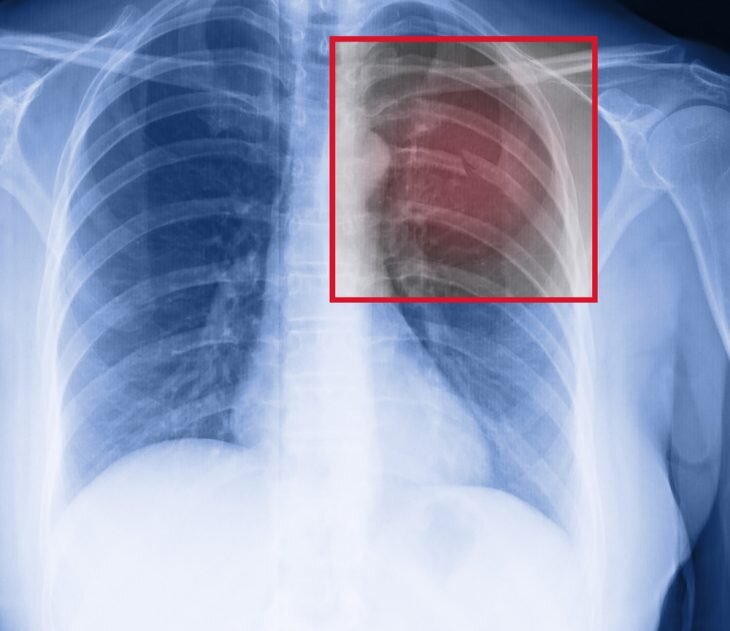

Переломы ребер могут быть односторонними и двухсторонними, единичными и множественными, со смещением и без оного, открытыми и закрытыми. Опасность представляют травмы, которые сопровождаются повреждением внутренних органов и нарушением дыхания. Но, диагностировать перелом может только специалист – на основе внешнего осмотра и рентгенографии.

• Пневмоторакс – костные фрагменты травмируют легкое, вследствие чего происходит нарушение целостности плевральной оболочки и тканей. Нарушается процесс дыхания, воздух начинает скапливаться между наружным и внутренним листками плевры. Возникает дыхательная недостаточность, что требует уже хирургического вмешательства.

• Гемотракс – в плевральной области происходит скапливание крови. Оно затрудняет дыхание, а также способствует развитию застойных процессов и падению альвеолярной активности легкого.